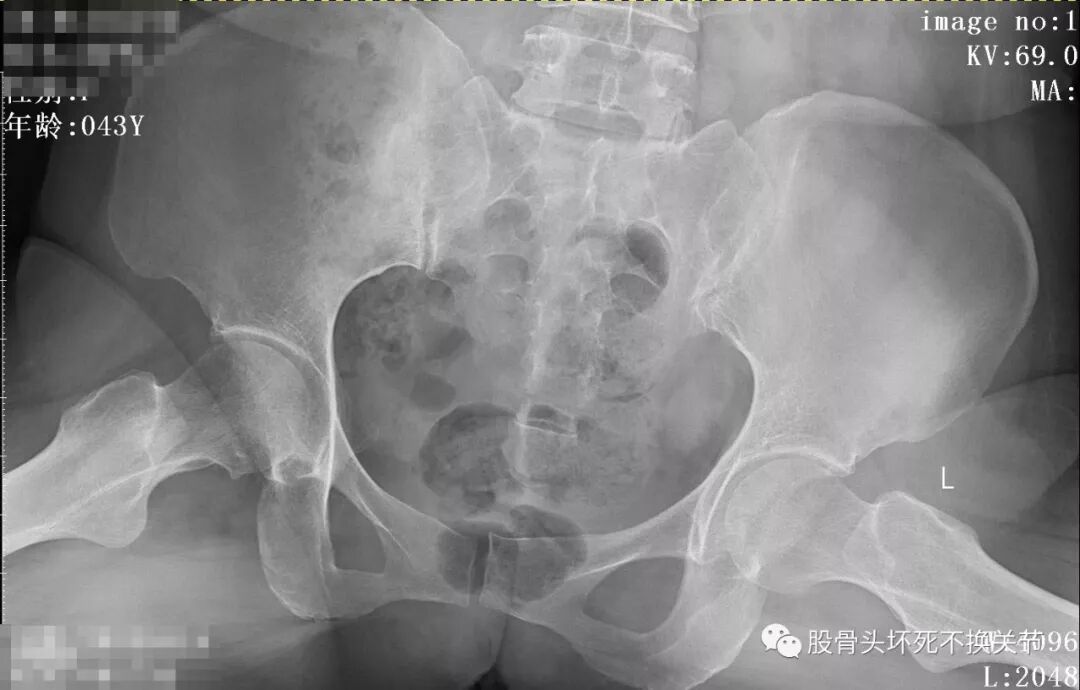

先看一下X光片:

骨盆正位片

骨盆蛙位片

从这些歪斜的X线片子可以看到,双髋关节并无特殊表现,双侧骶髂关节似乎轻微硬化(对于42岁生过孩子的女性来讲,不首先考虑病理原因);仔细研判放大了的右髋关节正位、蛙位片,可发现股骨头边缘轮廓并不是特别光整,与对侧相比右侧股骨近端整体骨密度低于对侧,对于一个长期患病、缺乏活动的关节来讲,不足为道,很常见。